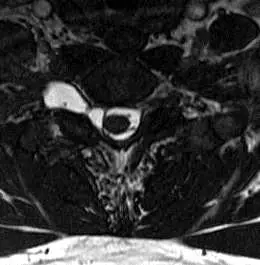

29 歲男性在⾞禍後發現右上肢無⼒與⿇痺,圖為頸椎的磁振造影影像( T2WI ),下列敘述何者錯誤?

本題提供頸椎 T2 加權影像(T2WI)橫軸切面(axial view),可見以下影像特徵:

- 脊髓中央呈低訊號,兩側脊髓旁可見正常椎間孔及神經根走行

- 右側(影像左方)可見一圓形/卵圓形亮訊號(高訊號)液體囊腔,位於椎管旁、緊鄰硬脊膜外側

- 此高訊號囊性病灶的訊號特性與腦脊髓液(CSF)相同,呈均勻的 T2 高訊號

- 囊腔位置與右側神經根離開脊髓的位置相符

- 對側(左側)結構對稱正常,無類似病灶

影像診斷: 上述右側椎管旁的 CSF 訊號囊腔,在車禍後臂神經叢傷害的臨床情境下,高度符合**假性脊髓膜膨出(pseudomeningocele)**的典型 MRI 表現——因硬脊膜(dura mater)撕裂,CSF 漏出並積聚於椎旁,形成無真性膜壁(non-encapsulated)的液體囊腔。Pseudomen